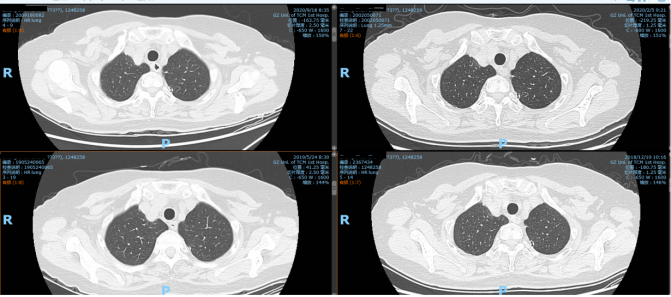

附:影像资料

2020年9月18日复查CT,对比2020年2月5日CT,提示:1.左下肺癌根治术后改变,未见明显肿瘤复发征象。左上肺后段少许纤维钙化及小结节,甲状腺肿大,同前。建议定期复查。2.老年性脑改变,余颅脑、颈部CT未见明显异常。